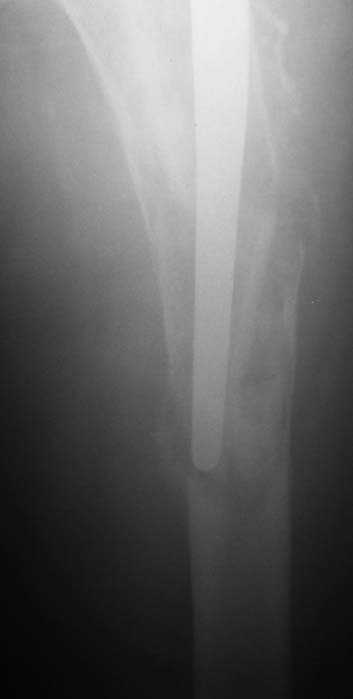

Мужчина, 39 лет.По поводу двустороннего асептического некроза головок бедренных костей последовательно выполнено тотальное эндопроезирование левого (1998 г), затем правого (1999 г) тазобедренных суставов.

11/07/04

С 2001 г отмечает нарастающие боли в левом бедре. Предполагается удаление протеза, удаление цемена из канала бедра, пластика дефекта бедренной кости.